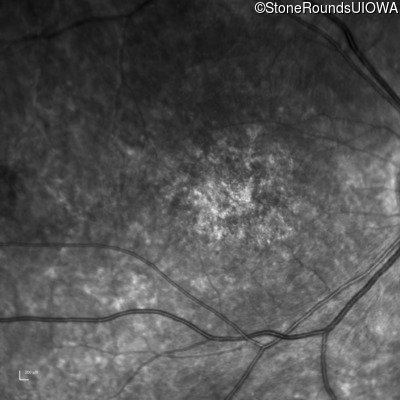

AR Stargardt Disease (IIA)

Age at visit: 15 years

This 15 year old female recalls not being able to see the black board in 2nd grade despite sitting in the 2nd row.

AR Stargardt Disease ABCA4 Val256Val GTG>GTT His1118Asp CAC>GAC AR